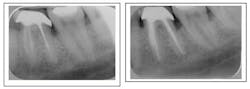

Case corrected with retreatment and root resection surgery (overfill)